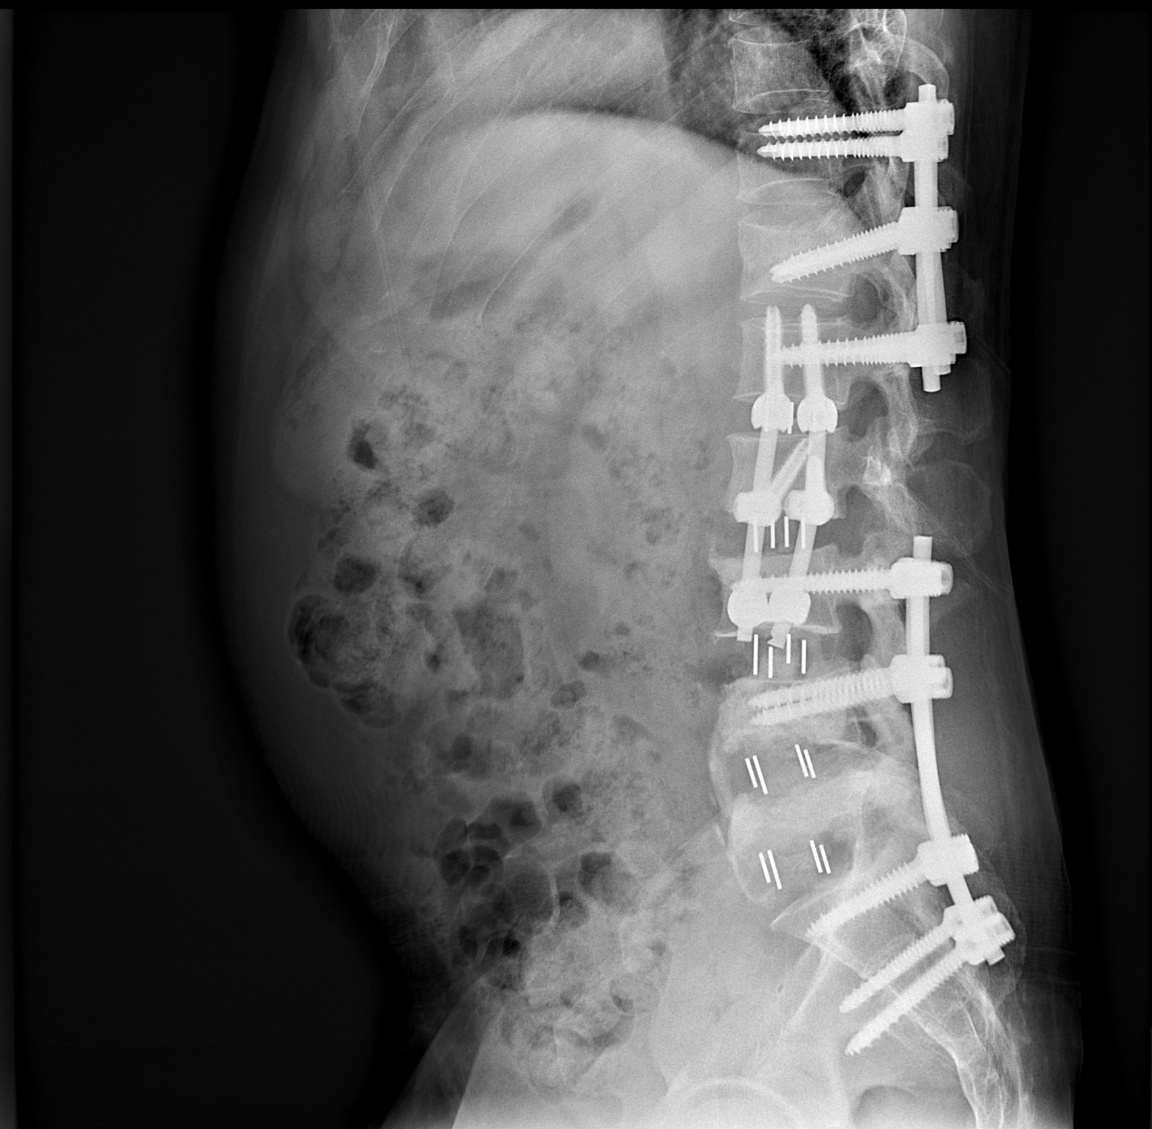

【医学上风险最大的手术是什么样子的?】下面三张图是人类胸椎的横断面。骨头中间圆形

老人家的脊柱骨折首选微创手术,不建议保守治疗。看这个老太太,躺着做CT显示胸12

不幸的颈椎病人:四年前在某顶级大医院做的开放手术,前后路切口20厘米,花费十几万